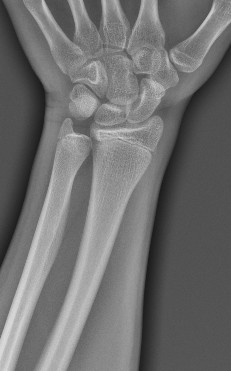

Need some high IQ to tell me if they're still open

Chatgpt told me they're still open but really close to fusing

open not for a long time though

Your good bro, distal radius open but distal ulna closed . How old are you?